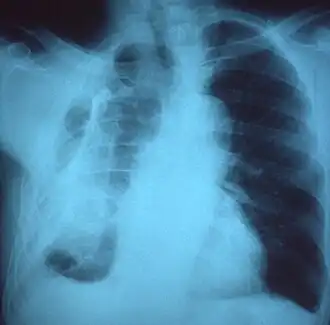

Fibrotórax extenso do lado esquerdo -

Radiografia de tórax exibindo opacificação não homogênea da metade esquerda do tórax que é fibrotórax -